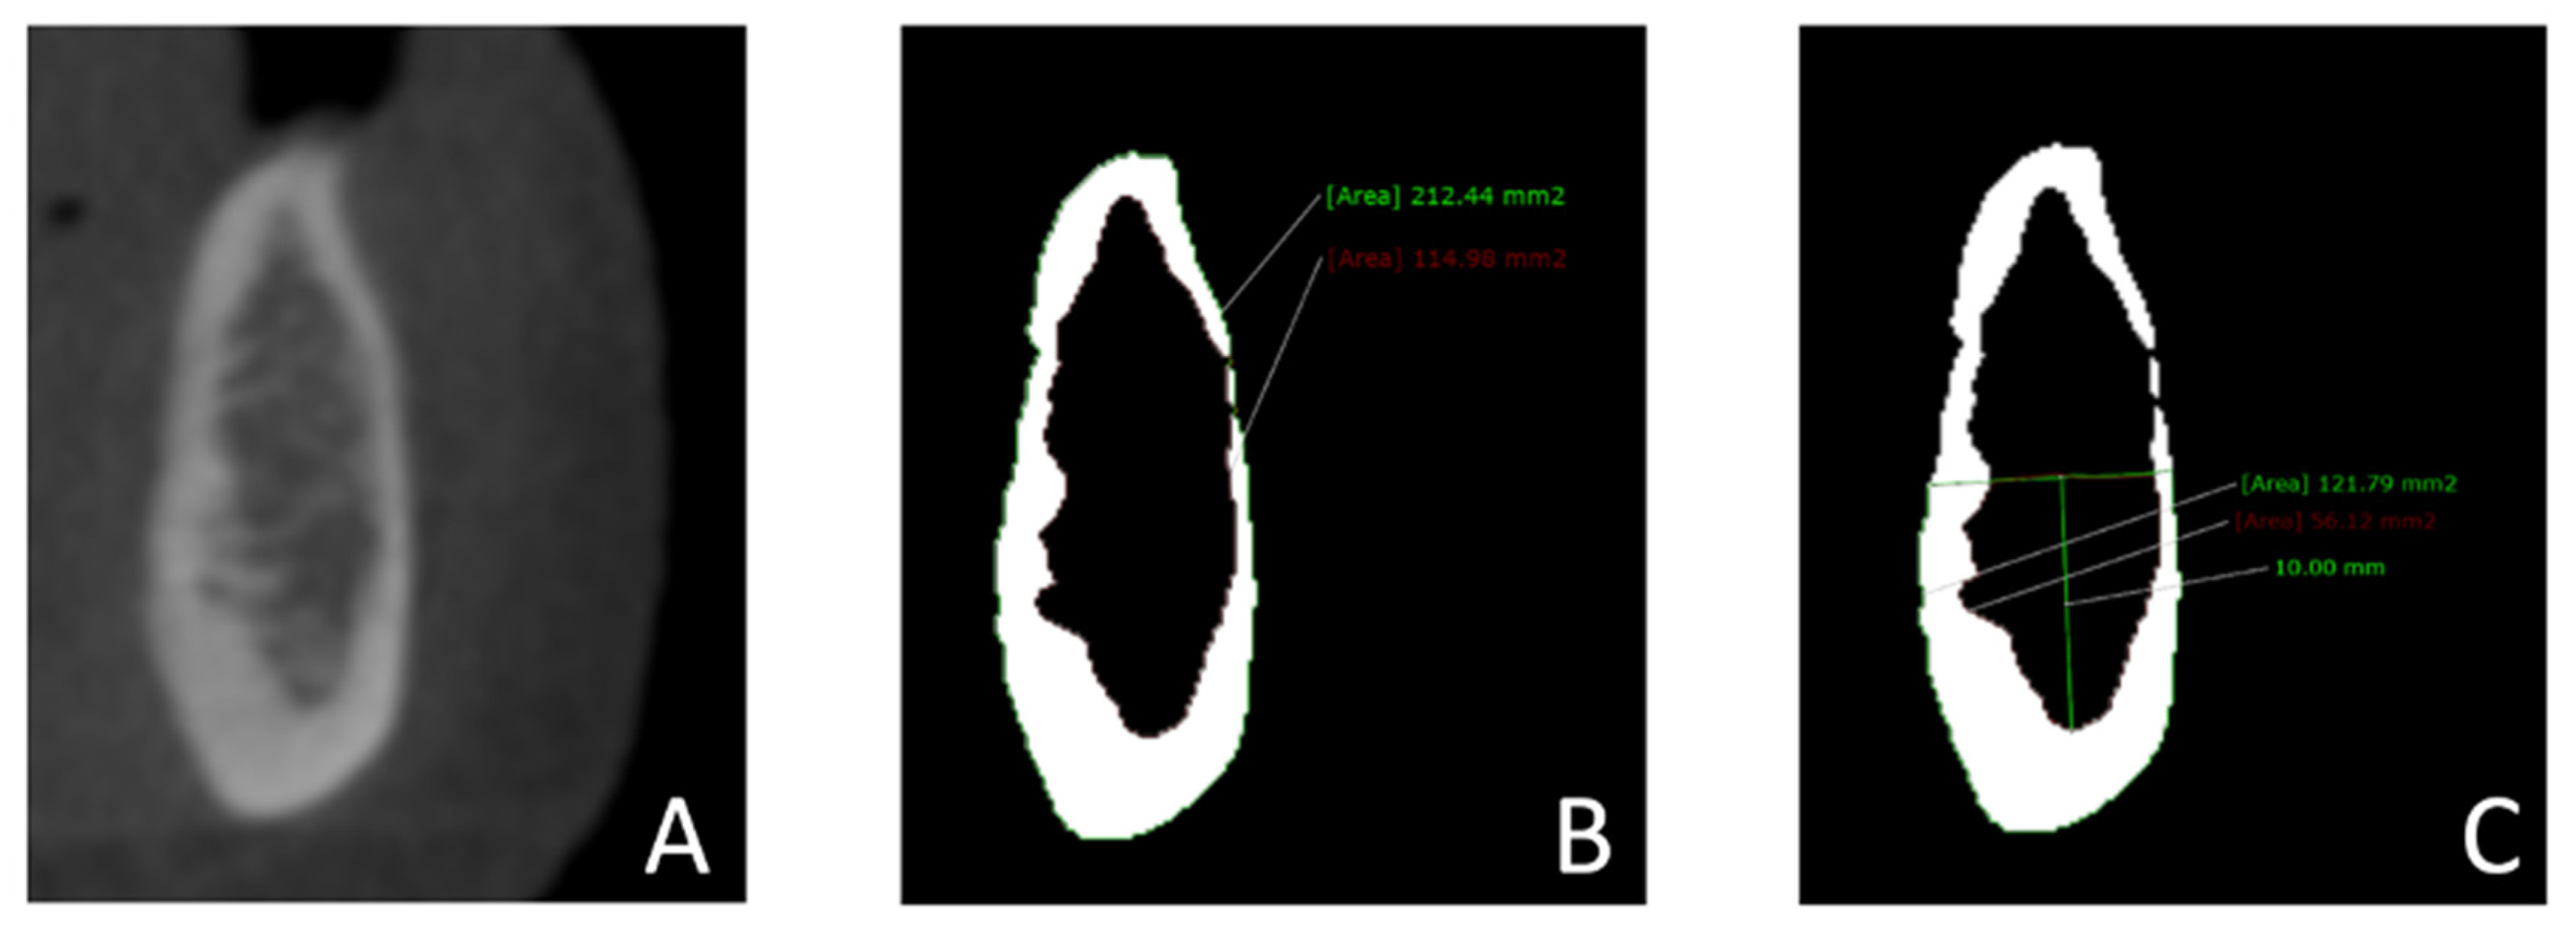

2.5. CBCT Measurements